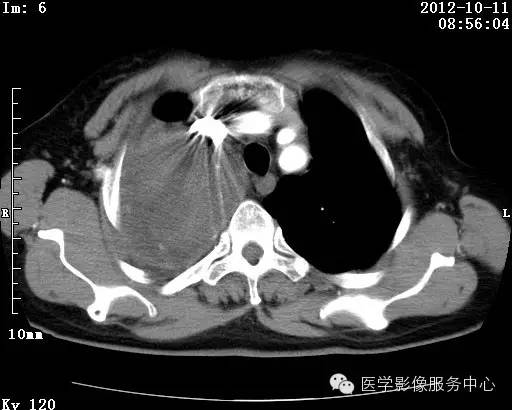

【病例】右肺巨大错构瘤1例CT影像表现

病史:女 65岁咳嗽咳痰 右肺巨大肿块就诊。

错构瘤的发病年龄多数在40岁以上,男性多于女性。 绝大多数错构瘤(约80%以上)生长在肺的周边部,紧贴于肺的脏层胸膜之下,有时突出于肺表面。其特征钙化为爆米花样钙化,内有脂肪软骨成分等等。最常见的部位是胸膜下肺实质内,其次为主支气管或肺叶、肺段支气管内。

理论上肺错构瘤为良性肿瘤,其结节形态、边界、与胸膜关系、与肺门关系、淋巴结肿大及与血管关系均应符合良性肿瘤的特点。

由于不典型错构瘤极易误诊为周围型肺癌和/或结核球,故应与二者鉴别。

结核球患者既往病史中可能有明确的肺结核病史,周围多可见卫 星病灶,增强扫描无强化或仅有包膜强化,此外纵隔 肺门淋巴结多有钙化征象;

周围型肺癌绝大多数边界不光整, 可见短毛刺,钙化不常见,爆米花样钙化更罕见,而 且往往合并有纵隔肺门淋巴结增大增多,患者临床症状较为明显。